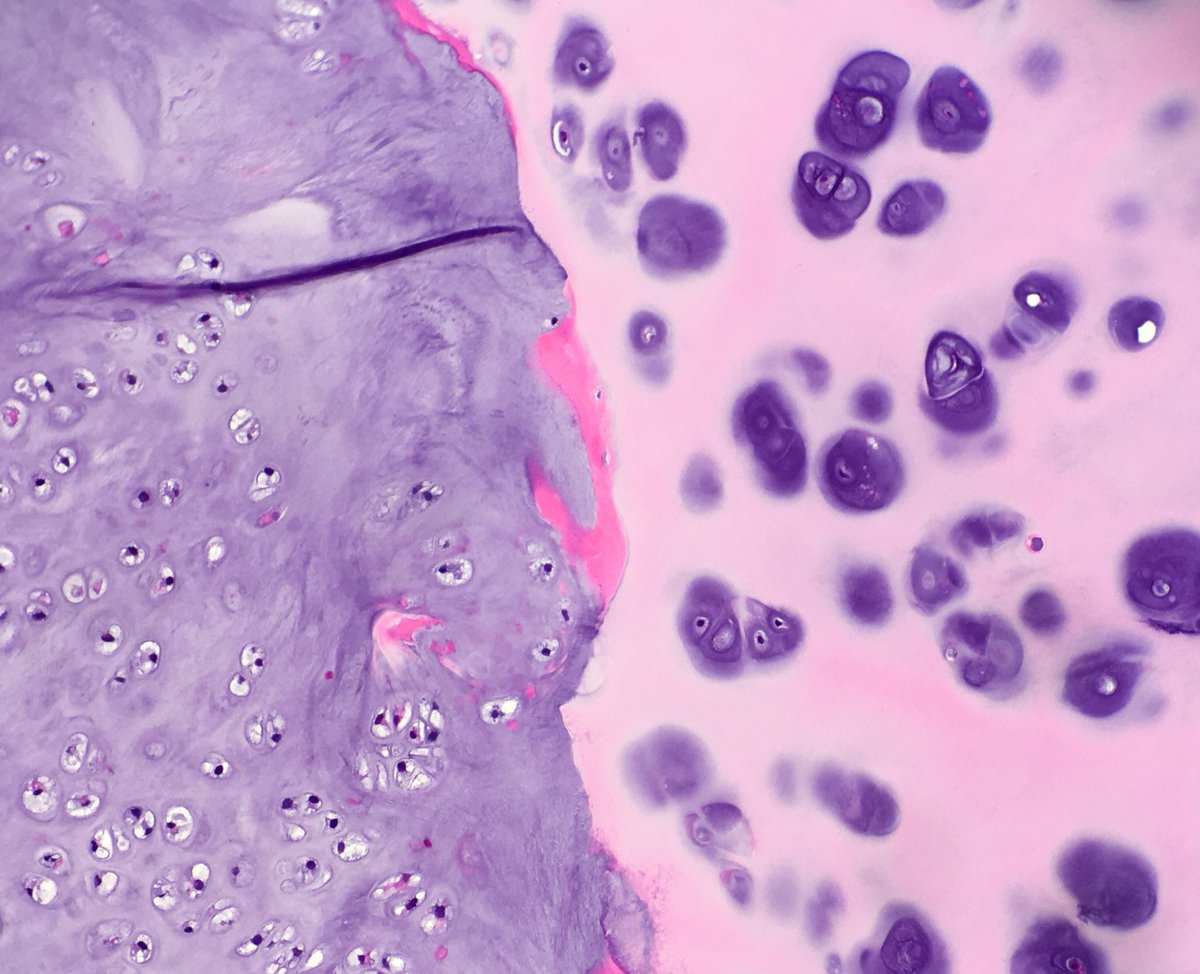

A very photogenic tumor 😊 Chondrosarcoma (L) ot the cricoid cartilage (R).

april_path's tweet image. A very photogenic tumor 😊

Chondrosarcoma (L) ot the cricoid cartilage (R).